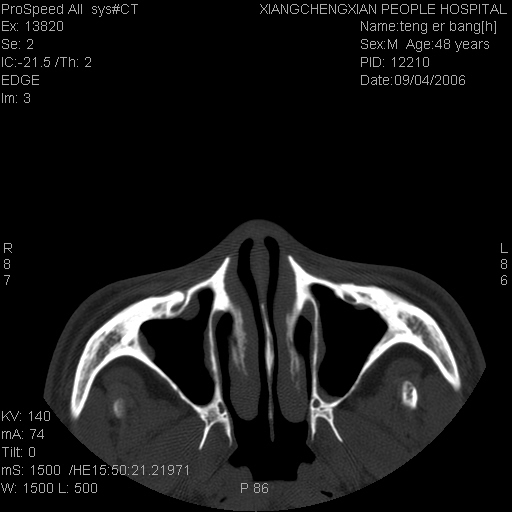

患者,男,以头面部外伤后头疼1小时为主诉入院,患者1小时前被他人打伤头部及左侧面部,眼睑无水肿,左侧面部肿胀压疼,未触及骨擦音。专科检查:耳鼻喉未见异常。

ct:平扫+冠扫:双侧鼻骨对比,冠扫s6#示右侧鼻骨尖部可见线状低密度影,边缘光滑,并见硬化.软组织未见肿胀.

诊断意见:鼻额缝(鼻骨与上颌骨额突缝),但个别同志认为是骨折.因此请同行们会诊.多谢了!

正常鼻颌缝。软组织无肿胀。鼻腔无积液积血。鼻骨光滑规整无中断。均不支持骨折。

正常的,双侧对称.边缘光整,且逢等宽.

正常鼻颌缝。软组织无肿胀。鼻腔无积液积血。鼻骨光滑规整双侧对称。均不支持骨折。